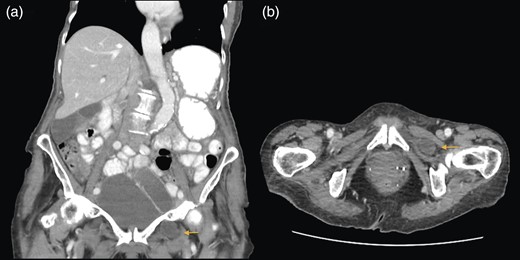

A 88-year-old woman presented to the ED with abdominal pain, vomiting, right hip pain and diarrhoea. Medical co-morbidities include ischaemic heart disease, hypertension and bilateral osteoarthritis of the hip. Her surgical history includes three Caesarean sections, open cholecystectomy, umbilical hernia repair and left mastectomy for breast cancer. A computed tomography (CT) abdomen revealed small bowel obstruction due to the right OH (Fig. 1) and evidence of a small left OH. A trial of conservative management was made for patient due to her age, multiple co-morbidities and patient's wishes. Bowel obstruction resolved with conservative management. The patient re-presented 1 month later with small bowel obstruction and pain radiating down medial left leg. There were no clinical signs of intestinal ischaemia. Abdominal x-ray was consistent with small bowel obstruction (Fig. 2) and CT abdomen revealed transition point at left OH (Fig. 3). A decision was made to proceed with midline laparotomy and bilateral OH repair. Intra-operatively, there was a large right OH containing a small bowel, which was reduced, and a bard polypropylene mesh plug inserted into the defect and fixed with prolene interrupted sutures. The left OH was smaller and was repaired primarily with prolene. The patient made an unremarkable recovery, and she was discharged 3 days after the operation. No recurrence was noted within a year of follow-up.

(a and b) Small bowel obstruction secondary to a right OH. (a) Coronal and (b) axial.